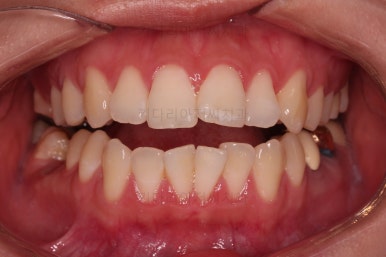

전후 비교 해볼게요.

입안의 모습은 더할나위 없이 잘 개선되었고요.

상하좌우 이 뽑은 위치와 크기가 달라 이정도 중앙선은 매우 잘 맞는 상황인거고요.

얼굴모습도 옆라인이 매우 좋아졌죠.

입이 들어가고 턱선이 살아나게끔 해드렸어요.

임플란트도 안해도 되면서 사랑니까지 잘 사용하고 2년 반 밖에 치료기간도 안걸린 매우 좋은 치료였다고 생각되어집니다.